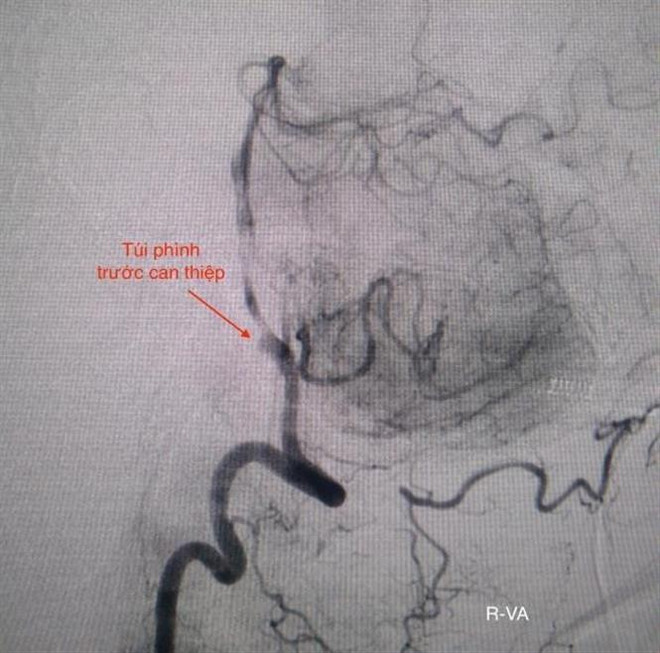

Cứu sống bệnh nhân hai lần ngưng tim do vỡ túi phình mạch máu não ảnh 2Hình ảnh túi phình động mạch trước can thiệp. (Ảnh: TTXVN phát)

Kết quả CT-scan sọ não và DSA mạch máu não cho thấy bệnh nhân bị xuất huyết khoang dưới nhện do vỡ túi phình đốt sống bên phải.

Êkíp can thiệp nội mạch do bác sỹ Trịnh Thành Tín và cộng sự đã tiến hành đặt 3 coil (vòng xoắn kim loại) để bít túi phình.

Sau gần 2 giờ, các bác sỹ đã bít hoàn toàn túi phình mạch não và tái thông dòng máu trở lại bình thường. Bệnh nhân được chuyển đến Khoa Hồi sức tích cực-chống độc để hồi sức nội khoa sau can thiệp.